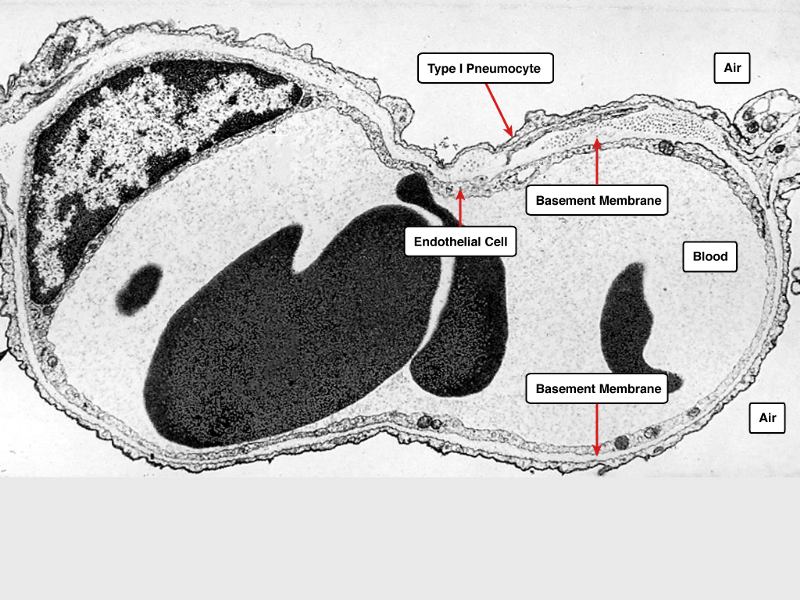

Trace the air flow of respiratory system starting with the nostrils.

What path does a molecule of oxygen take to reach the blood?

What sights will it see along the way?

- Outside air

- ??

- ...

- Toes

Path of O2

- List complete

- With layers

- And cells

- And function of each

- By studying and labelling images